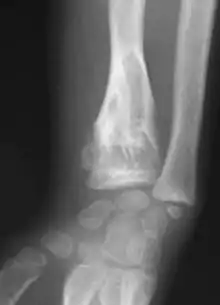

| X-ray image showing enchondromas localized in the lower part of the radius of a 7-year-old girl with Ollier disease. | |

X-ray showing enchondromas localized in the lower part of the radius of a 37-year-old patient affected with Ollier disease